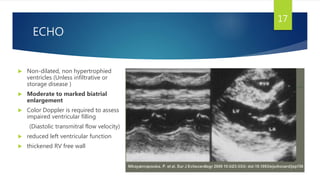

ECHO

 Non-dilated, non hypertrophied

ventricles (Unless infiltrative or

storage disease )

 Moderate to marked biatrial

enlargement

 Color Doppler is required to assess

impaired ventricular filling

(Diastolic transmitral flow velocity)

 reduced left ventricular function

 thickened RV free wall

17

ECHO  Non-dilated, nonhypertrophied ventricles (Unless infiltrative or storage disease )  Moderate to marked biatrial enlargement  Color Doppler is required to assess impaired ventricular filling (Diastolic transmitral flow velocity)  reduced left ventricular function  thickened RV free wall 17